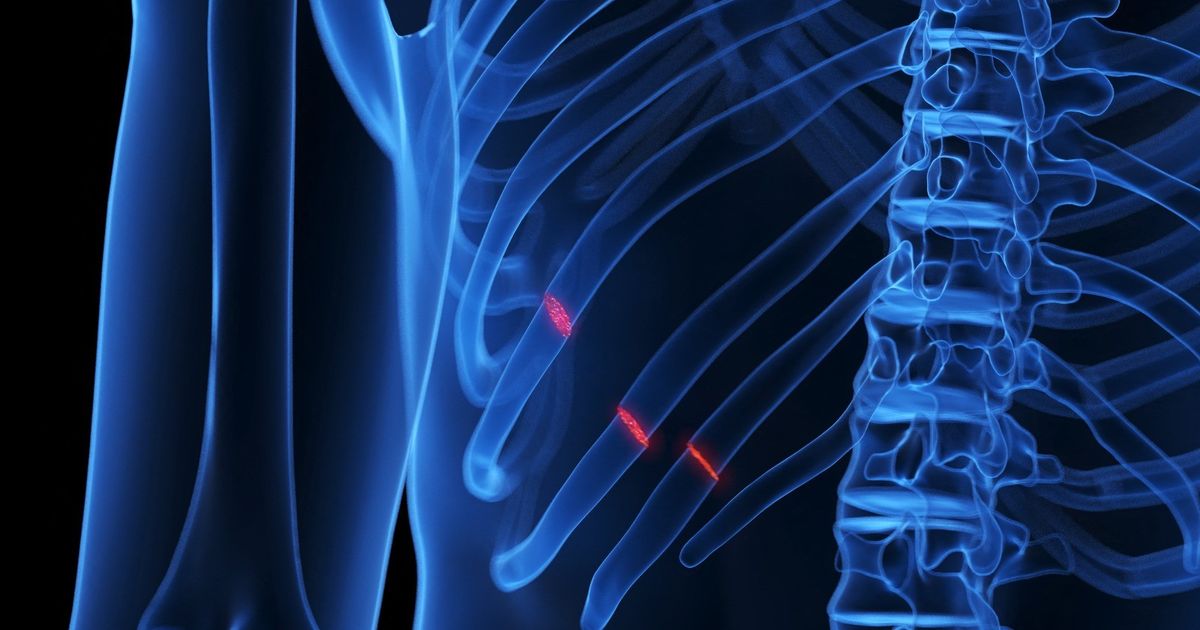

Ribs fractures are a common injury that occurs when one of the bones of the rib cage is broken or rupture. The most common reasons are violent shocks due to fall crashes, car accidents or sports that include physical friction. Most rib fractures are nothing but cracks. Although the ribs are painful, the problems that can cause the broken ribs. The acute edges of bone fractures can damage the most important blood vessels or lungs and other organs of the body. The ribs usually cure within about 6 weeks. There is necessary pain to breathe deeply and avoid lung problems such as pneumonia. Symptoms of rib fractures differ symptoms from rib fractures, and the following things can cause pain if there is a broken rib, or make the pain more: take a deep breath. Click the affected area. Bend or wrap the body. If you visit the doctor, you should visit the doctor in the event of a pain (reluctant) in a part of the rib area to an accident, or have trouble breathing or feeling pain as you breathe deeply. Immediately ask for medical help If you experience pressure, fullness or a contemporary pain in the middle of the breast, it takes longer than a few minutes or a pain that exceeds the chest area to the shoulder and arm. These symptoms can mean a heart attack. Causes of direct trauma ribs, such as car accidents, falls, child abuse or physical coherence, are the most common cause of rib fractures. The ribs can also be broken by the repeated shocks caused by sports such as golf and rowing, or caused by a long time by severe cough. The risk of ribs fractures. There are many factors that increase the risk of fractions of the ribs, including: osteoporosis, as this disease in which the bones lose their density to increase the possibility of being broken, in addition to the exercise of physical friction sports, such as hockey or American football, increases the possibility of chest, and one of the ribs infection increases the possibility of being broken. The complications of rib fractures can be damaged by blood vessels and internal body organs. In the event that more than one side is broken, the likelihood that exposure to these risks takes on. Complications vary according to the broken ribs. Possible complications include: rift in the main of the body known as the aorta. The sharp end can penetrate through a fraction into one of the first three ribs above the rib cage, one of the most important blood vessels, including the aorta. Lung fracture. Paint from a broken middle rib can cause a hole in the lung and cause the sinks. The spleen, liver or kidney tear. The lower two sides are rarely broken because of their ability to move more than the upper and middle ribs. But the ends of the broken underribs can cause the spleen, liver or kidneys to do serious damage. Prevention of rib fractures to prevent ribs should try to comply with the following: Protecting the body from mathematical injuries. Wear protective equipment during exercise that includes physical friction. Avoid the risk of falling inside the home. Eliminate chaos on the floors. Wipe off anything that is poured immediately. And use a rubber carpet during the shower. And make sure you lightly light at home. And make sure you have a rough lining in the mat or small carpets to prevent it from slipping. Strengthening bones. Obtaining a sufficient amount of calcium and vitamin D in the diet is important for bone strength. Make sure you get 1,200 milligrams of calcium and 600 IU vitamin D daily from food and nutritional supplements. The treatment of ribs breaks most of the broken ribs within 6 weeks. Reducing activities and ice creams on the environment can help heal and relieve pain regularly. Medicine is important ways to relieve pain. The inability to take a deep breath due to pain can lead to lung infection. In the event that oral medication is not useful, injection can be used for nerves that lead to ribs. Once the pain is controlled, some exercises can help you breathe deeper. Weakness of breathing can lead to pneumonia. * This content of Mayo Clinic

Fractures of ribs .. causes, symptoms and treatment